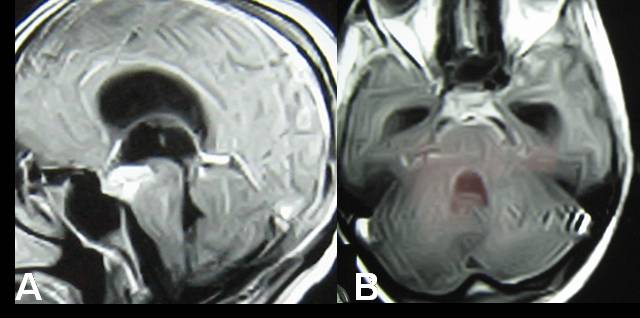

Third Ventricular and Interpeduncular Fossa Tubercular Abscess With Triventriculomegaly - Ventriculoscopic Surgical Management

Intracranial tuberculomas are rather common lesions in developing world.Tuberculomas are usually located in cerebellum, basal ganglia and cerebral hemispheres, particularly in frontoparietal region.Less common sites include the corpus callosum, quadrigeminal plate,the cerebellopontine angle, the retro-orbital region, the anterior optic pathway and the supraseller region.The central nervous system (CNS) involvement comprises approximately 1015% of all tuberculous infections. Brain tuberculosis is usually parenchymal. Intraventricular tuberculosis is very rare and only little number of cases has been reported. Intraventricular tubercular abscess is further rarer. Here we report a case of third ventricular tubercular abscess with triventriculomegaly that was managed by ventriculoscopic drainage and third ventriculostomy though preoperative diagnosis & surgical planning was different.